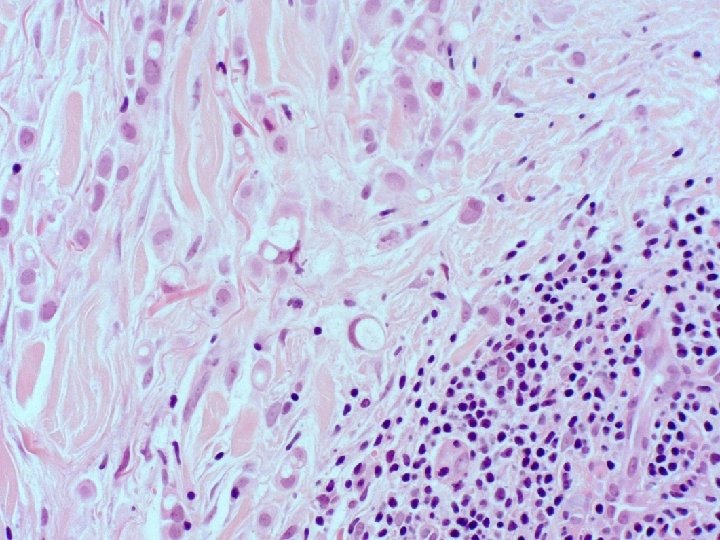

�Case number: 188 �Female aged 62. �? Multiple cysts posterior neck. �Specimen: Punch biopsy

�Case number: 188 �Female aged 62. �? Multiple cysts posterior neck. �Specimen: Punch biopsy �Macro: 3 x 3 x 4 mm punch biopsy.

Most popular diagnosis Malignant, probably metastatic lobular breast 9. 70